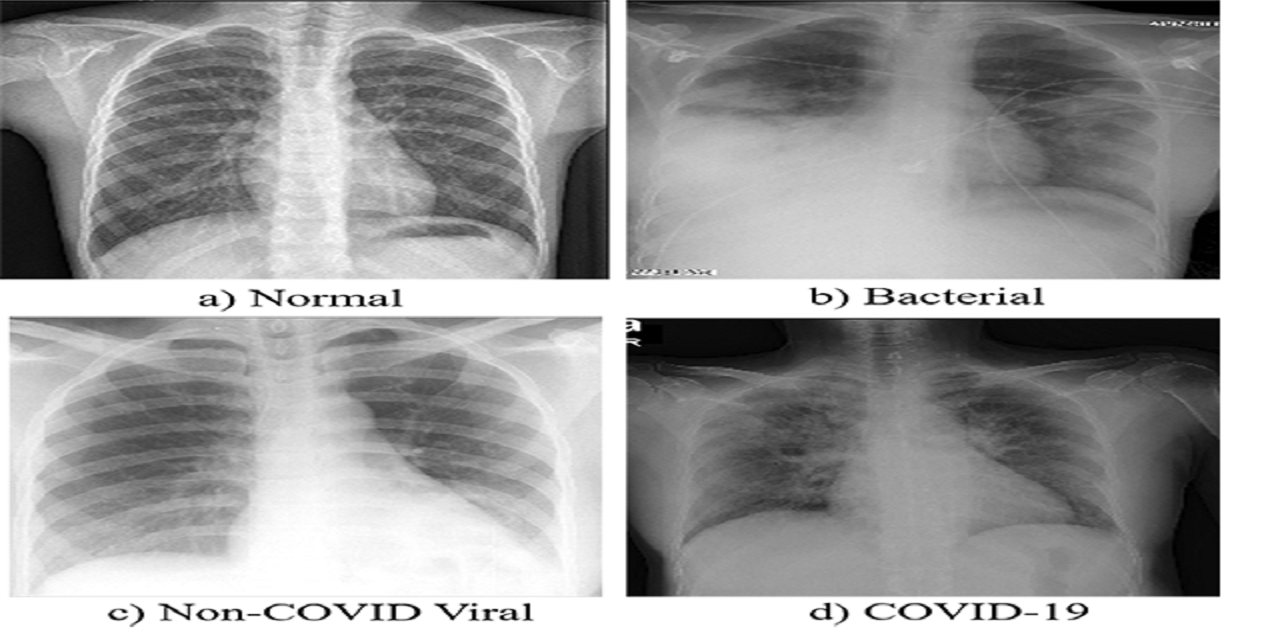

Chest X Ray Images Pneumonia Kaggle

Chest Xray Images Github Topics Github